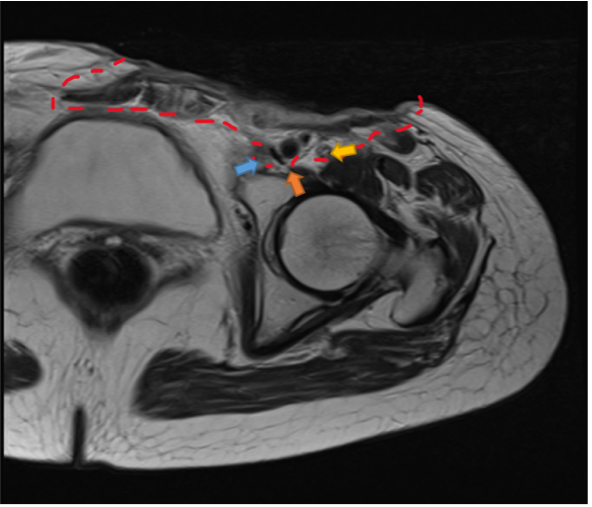

Histopathological examination revealed inflammatory granules formation with crusting on the surface. Tumor cells with chromatin-rich oval nuclei and a high nuclear-cytoplasmic ratio (N/C ratio) were observed to infiltrate and proliferate, forming irregular foci. The interstitium showed vitreous fibrosis. BCC was diagnosed (Figure 1B). Magnetic resonance imaging (MRI) revealed extensive soft tissue shadow in the left inguinal region, suggesting tumor invasion into the left femoral artery and vein. No enlarged lymph nodes were detected (Figure 2).